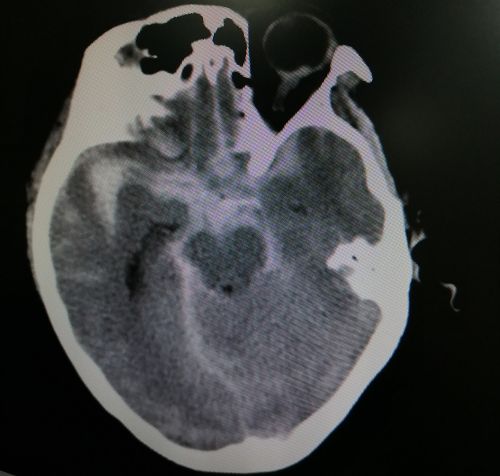

熊女士术前影像资料显示,蛛网膜下腔大量出血。

2020年6月11日,60岁的熊女士在家打麻将,胡了一把牌后,突然出现意识障碍,呼之不应。家人赶紧采用掐人中、搓手脚等土办法试图唤醒她,却不见效,立即将其送往就近的捷克论坛 。头部CT检查提示“蛛网膜下腔出血”,需立即转往上级捷克论坛 手术。而此时,熊女士已经陷入昏迷,为防止转运途中出现意外,只得进行气管插管处理。